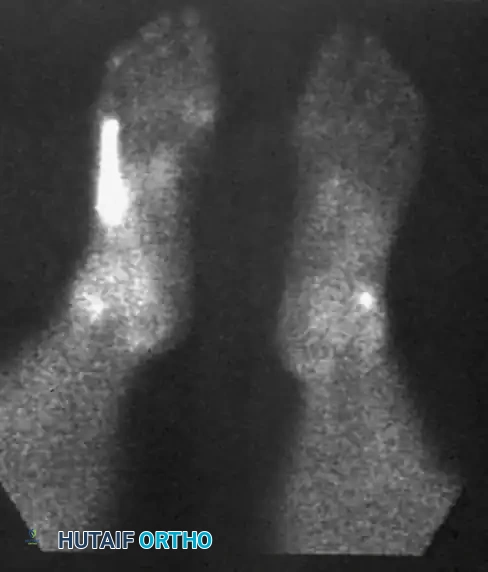

- Plain Radiographs: Weight-bearing anteroposterior, lateral, and mortise views of the ankle and foot are obtained to rule out fractures (e.g., "fleck sign" indicating SPR avulsion), os peroneum pathology, or varus hindfoot alignment.

Lateral radiographic view of the ankle.